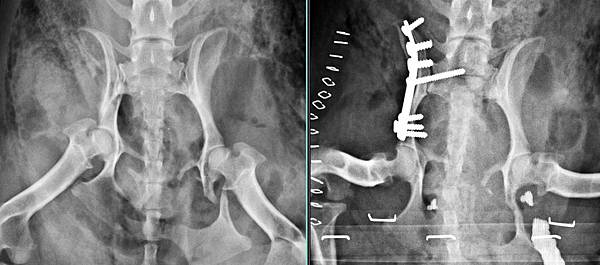

可以看到後半身被車子輾過去

經由手術後治療